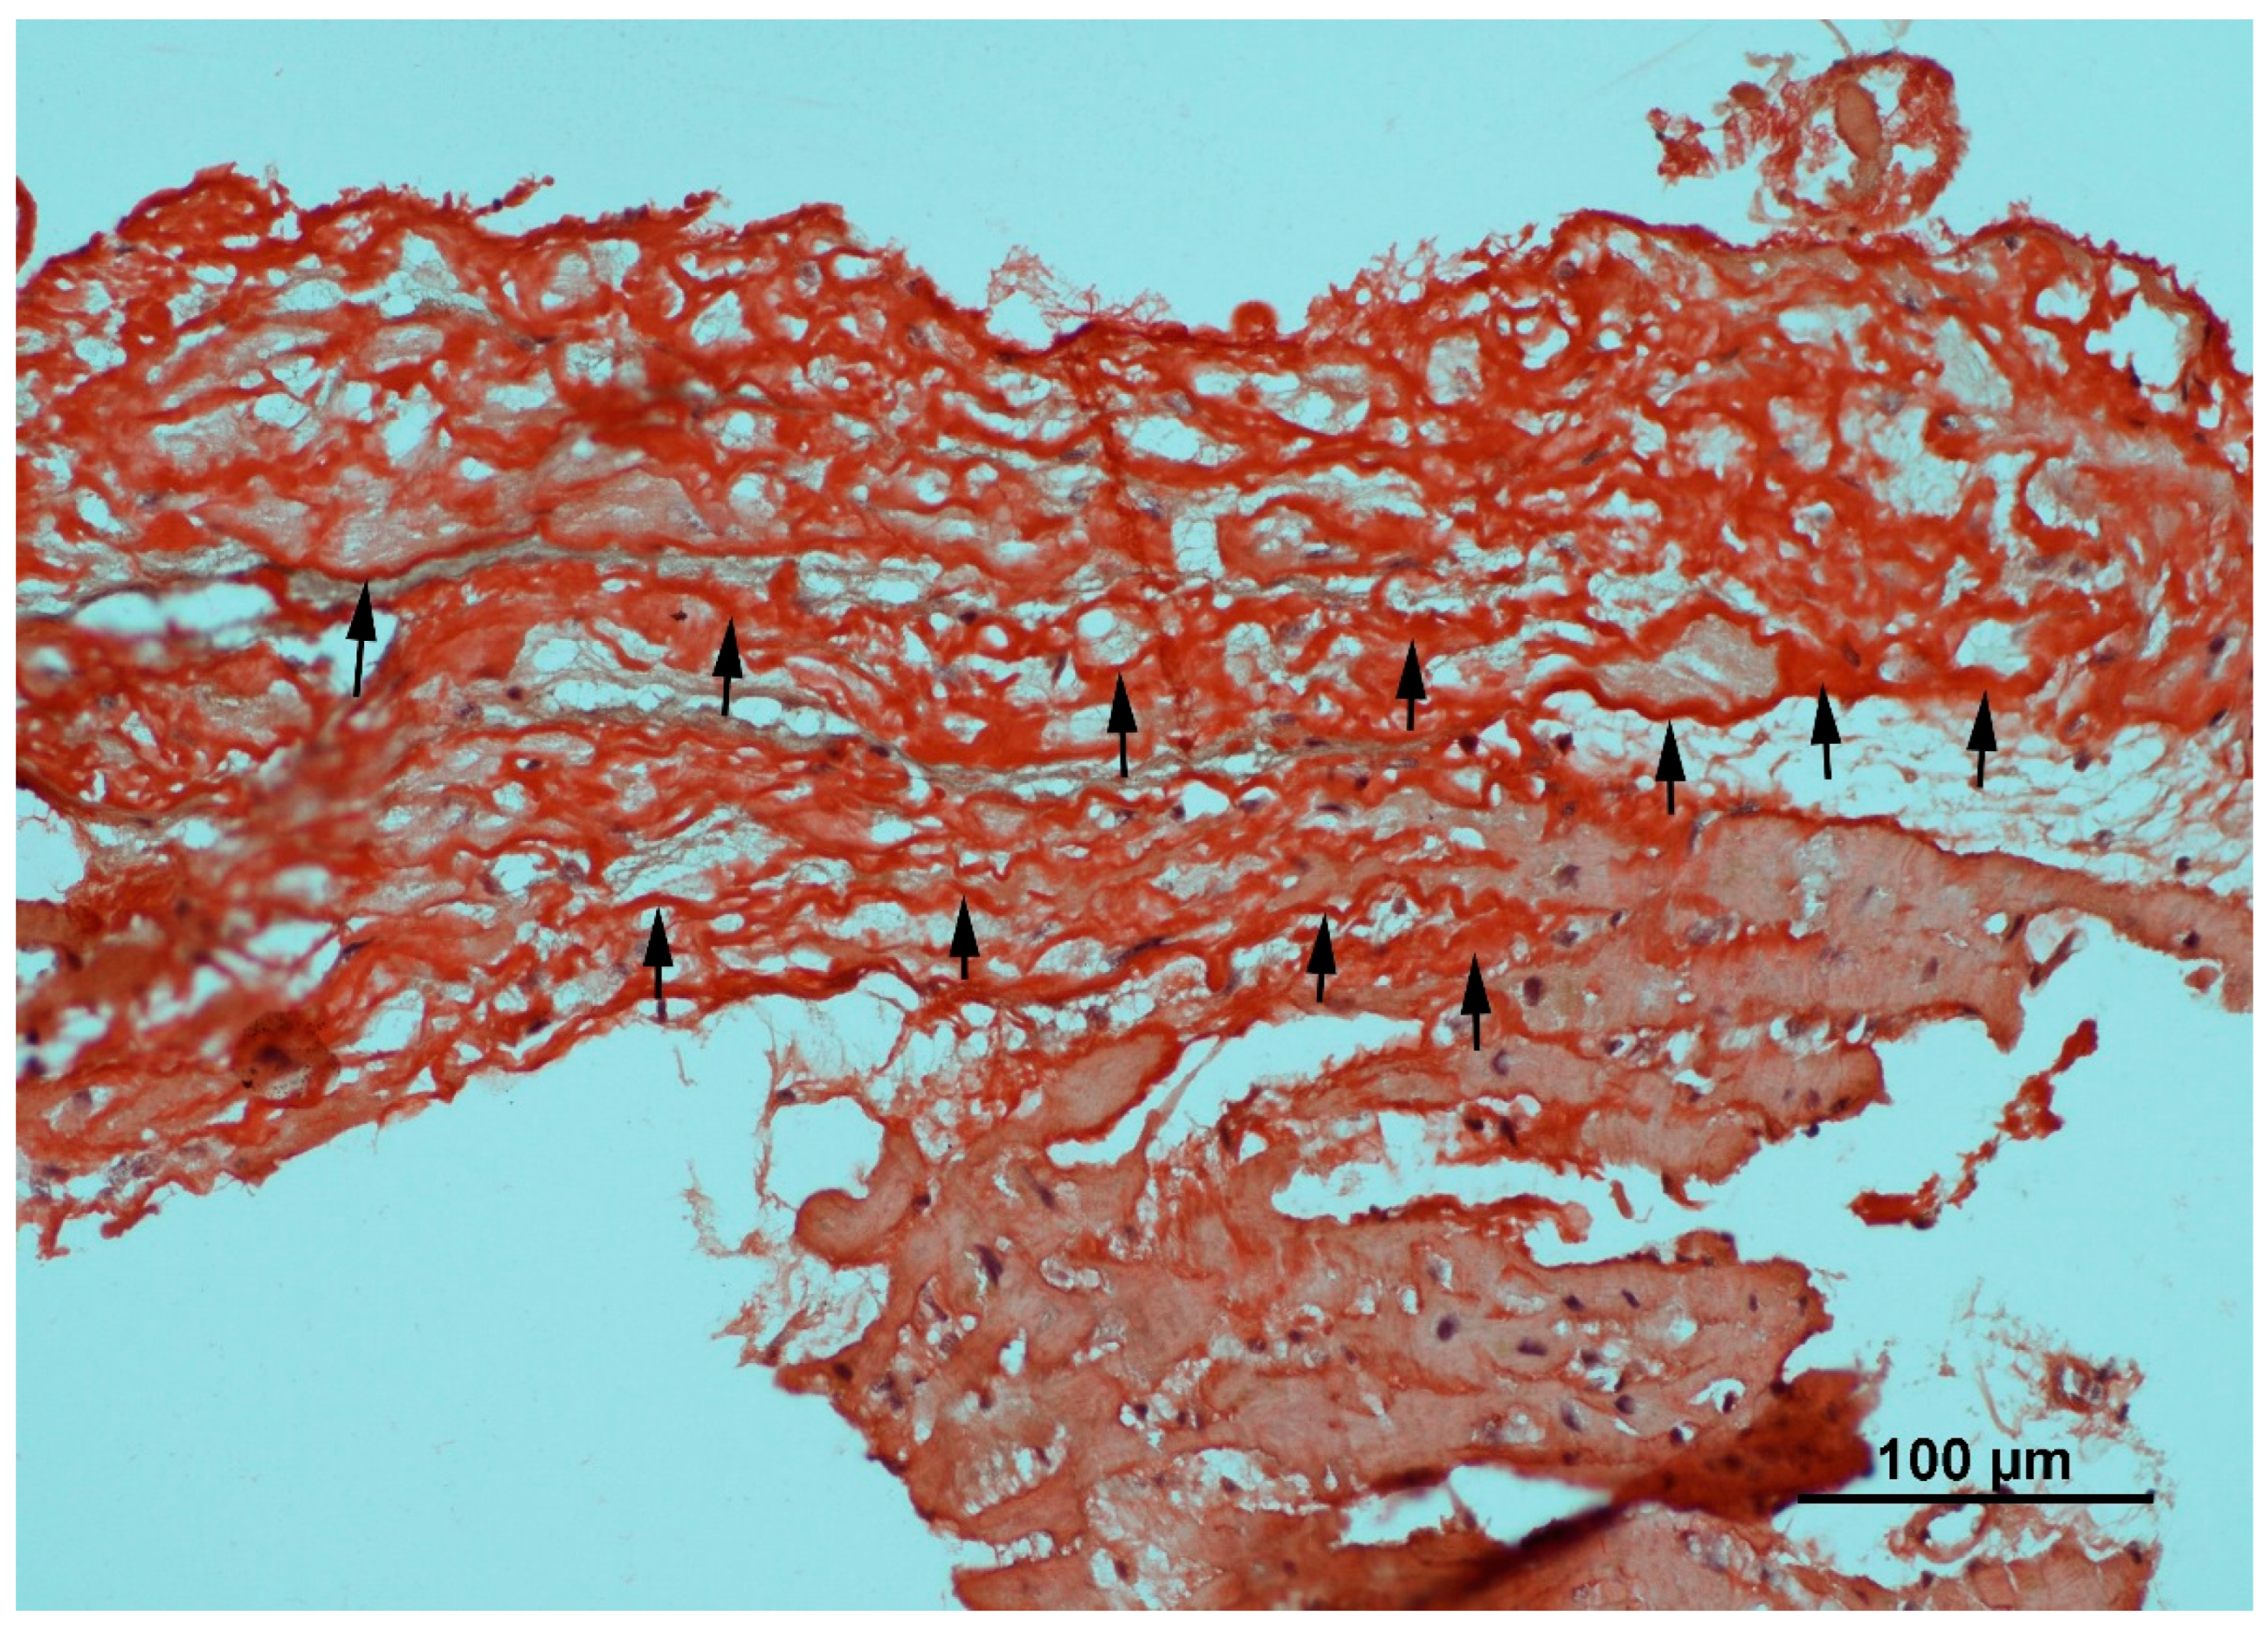

Congo red (CR) staining (Figure 1) is a histochemical technique used to detect amyloid deposits in tissue. The dye binds specifically to the β-sheet structure of amyloid fibrils, producing red staining under brightfield illumination and characteristic apple-green birefringence when viewed under polarized light between a crossed polarizer and analyzer. Tissue must be formalin-fixed, paraffin-embedded, sectioned (6–10 µm), deparaffinized, and rehydrated before staining. Hematoxylin may be added for contrast [28,29]. CR is highly specific for amyloid but cannot identify the protein subtype or quantify deposition. It may miss small deposits and occasionally produces background staining. For definitive diagnosis, CR is often combined with immunohistochemistry or mass spectrometry. Sensitivity can be improved using enhanced protocols, such as alkaline CR staining and digital analysis [30,31].

Figure 1.

Congo red histochemistry stain of myocardial tissue under brightfield microscopy. The black arrows indicate the deposition of amyloid fibrils, which appear as characteristic brick-red or salmon-pink amorphous material infiltrating the interstitial space between cardiomyocytes. Note the distinction between the avidly stained amyloid deposits and the pale, unstained surrounding connective tissue and myocytes.